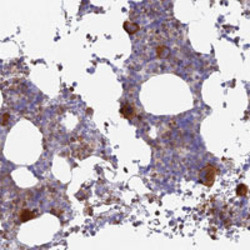

Supportive validation

- Submitted by

- Abnova Corporation (provider)

- Main image

- Experimental details

- Immunohistochemical staining of human bone marrow with STRN4 polyclonal antibody (Cat # PAB28128) shows strong cytoplasmic positivity in megakaryocytes at 1:50-1:200 dilution.

- Validation comment

- Immunohistochemistry (Formalin/PFA-fixed paraffin-embedded sections)